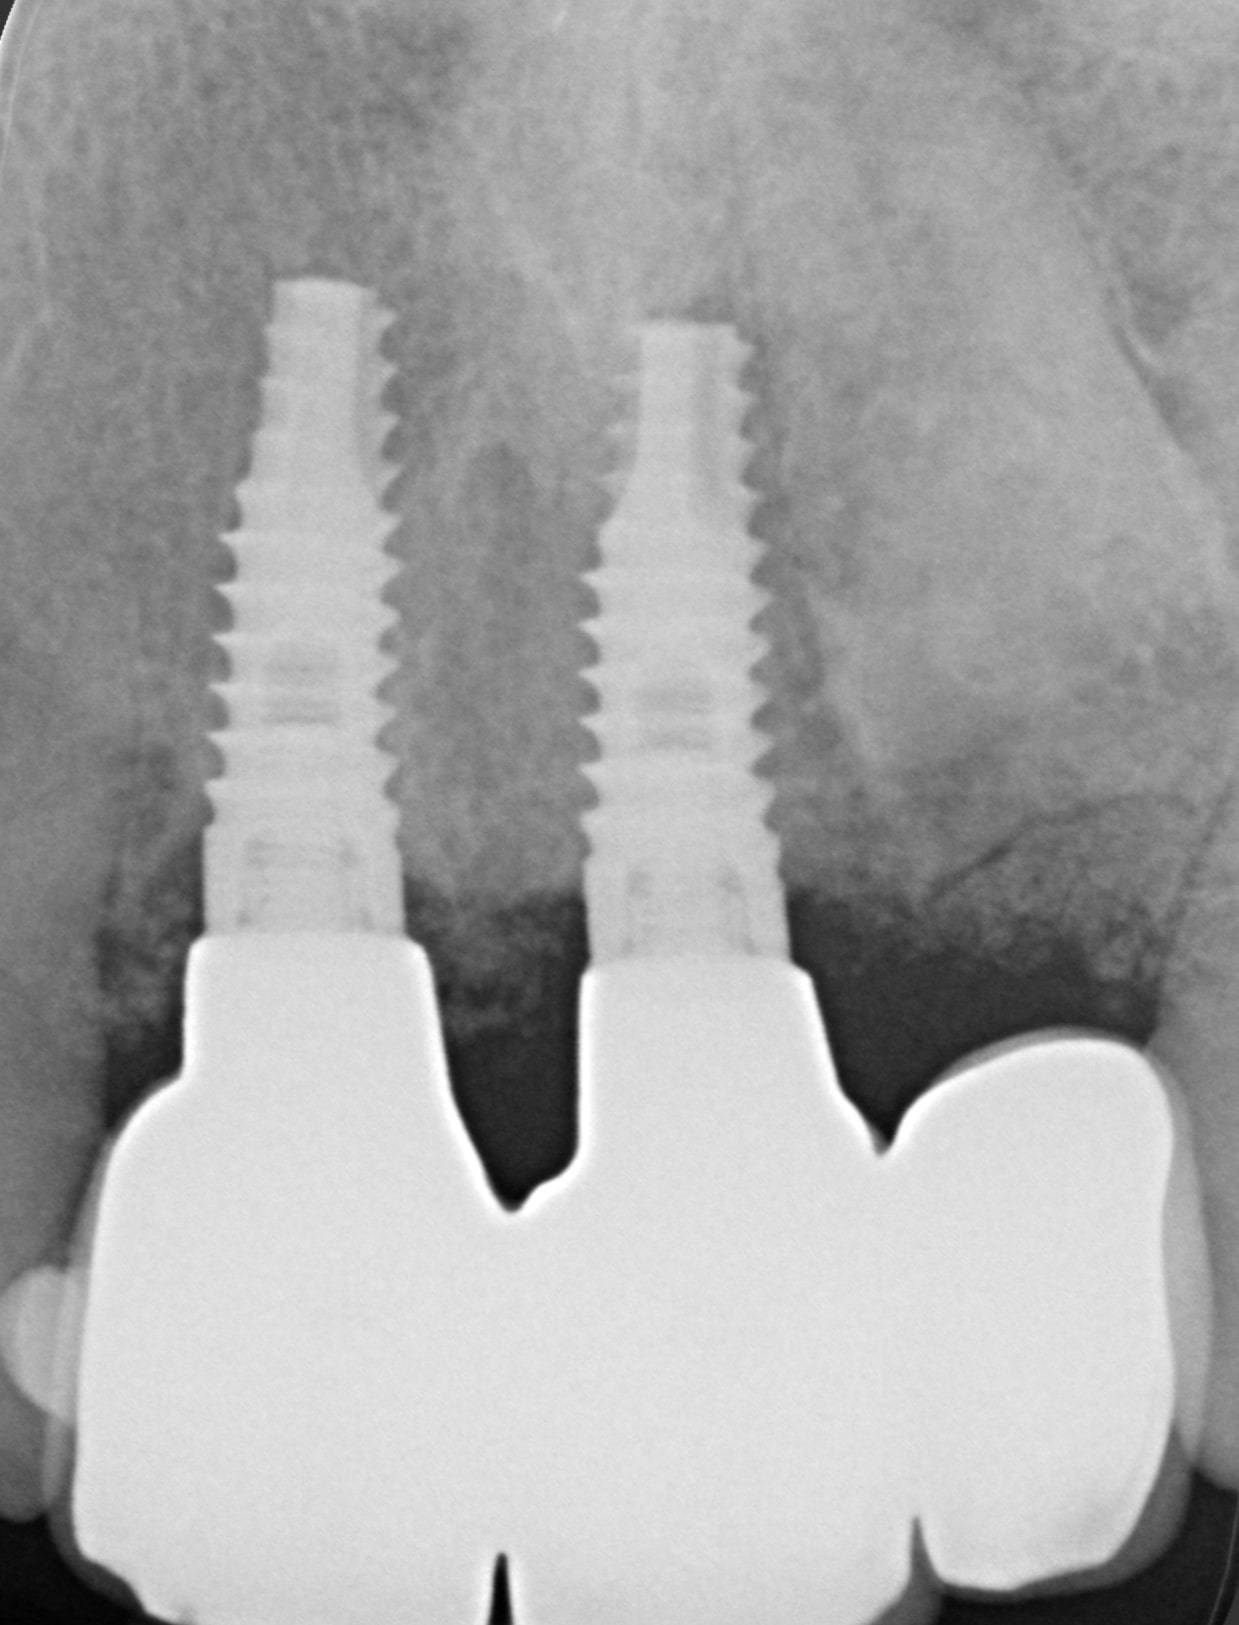

Guarda la foto successiva. Quel ponte di 3 denti sugli incisivi si muoveva così tanto che le rendeva la vita un dramma. Ho dovuto estrarle il vecchio ponte, inserire due impianti osteointegrati e fare quello che noi dentisti chiamiamo “rigenerazione ossea guidata”, per ricostruirle l’estetica naturale che vedi nella prima foto. Solo nella terza, la radiografia, puoi vedere cosa c’è dentro, al posto del suo denti ormai persi.